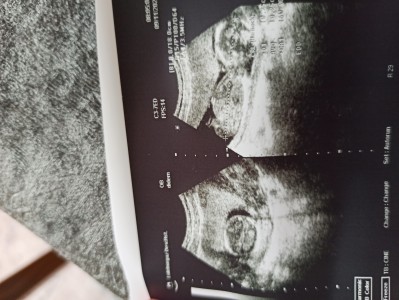

Arkadaşlar bu niye böyle top gibi yaa bı garip geldi bana bu ultrason ama doktor tabi herşey yolunda dedi bende herşeyden bı nem kapıyorum niyeyse böyle oldum pimpirikliyim gülmen bak top dedim diye

image

Gebelik haftası 16+0

Canım o top gibi olan kafatası.bebegin kafatası ayrı ölçülüyor üstteki de bebeğin boydan hali

Bebiş kafasını dönmüştür. Kafasının görüntüsüdür o top görüntüsü:) bende dün Hasteneye gittim bebegin burnu nerdeyse yok bende çok evhamliyim ama iyi düşünmek lazım kötüye yormayalım:)

Sol foto da bebegin kafasının ustten görünümü var. Sağ foto da yan durmuş gövdesi ama kafasını çevirmiş yüzü görünmüyor o yüzden. Sorun yok yani cnm. Zaten olsa doktor söylerdi merk etme.

Kollarıni kafasına çekiyor bacakları karnina çekiyor haliyle ultrasonda kol bacak görünmüyor gövde ve kafa görünüyor o yüzden top gibi gelebilit sana :)